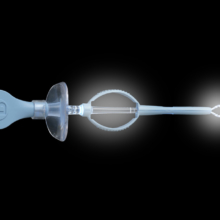

Texa Biomedicali seleziona i migliori prodotti nell’ambito del Monouso per Otorinolaringoiatra (ORL). Alta affidabilità e standard qualitativi in relazione alla vendita di Kit ORL sterili, curettes ORL, speculum monouso.